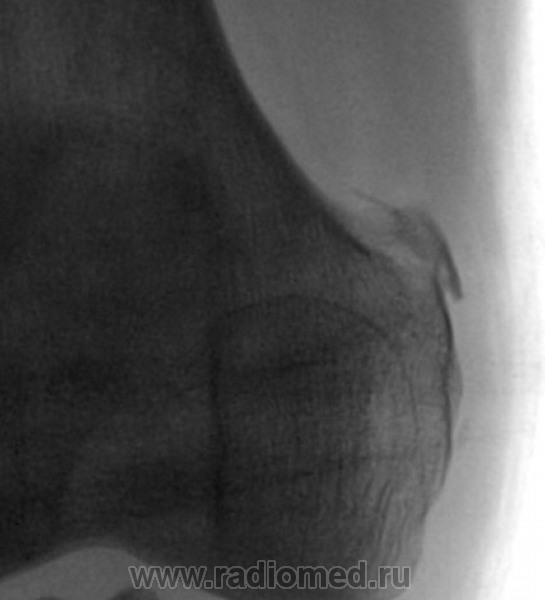

Помянем Штида

Зачем поминать. Лучше вспомнить.

А в диафизе ББК что?

Точно! Не инфаркт ли?

Угу, следствия.

Ничего.